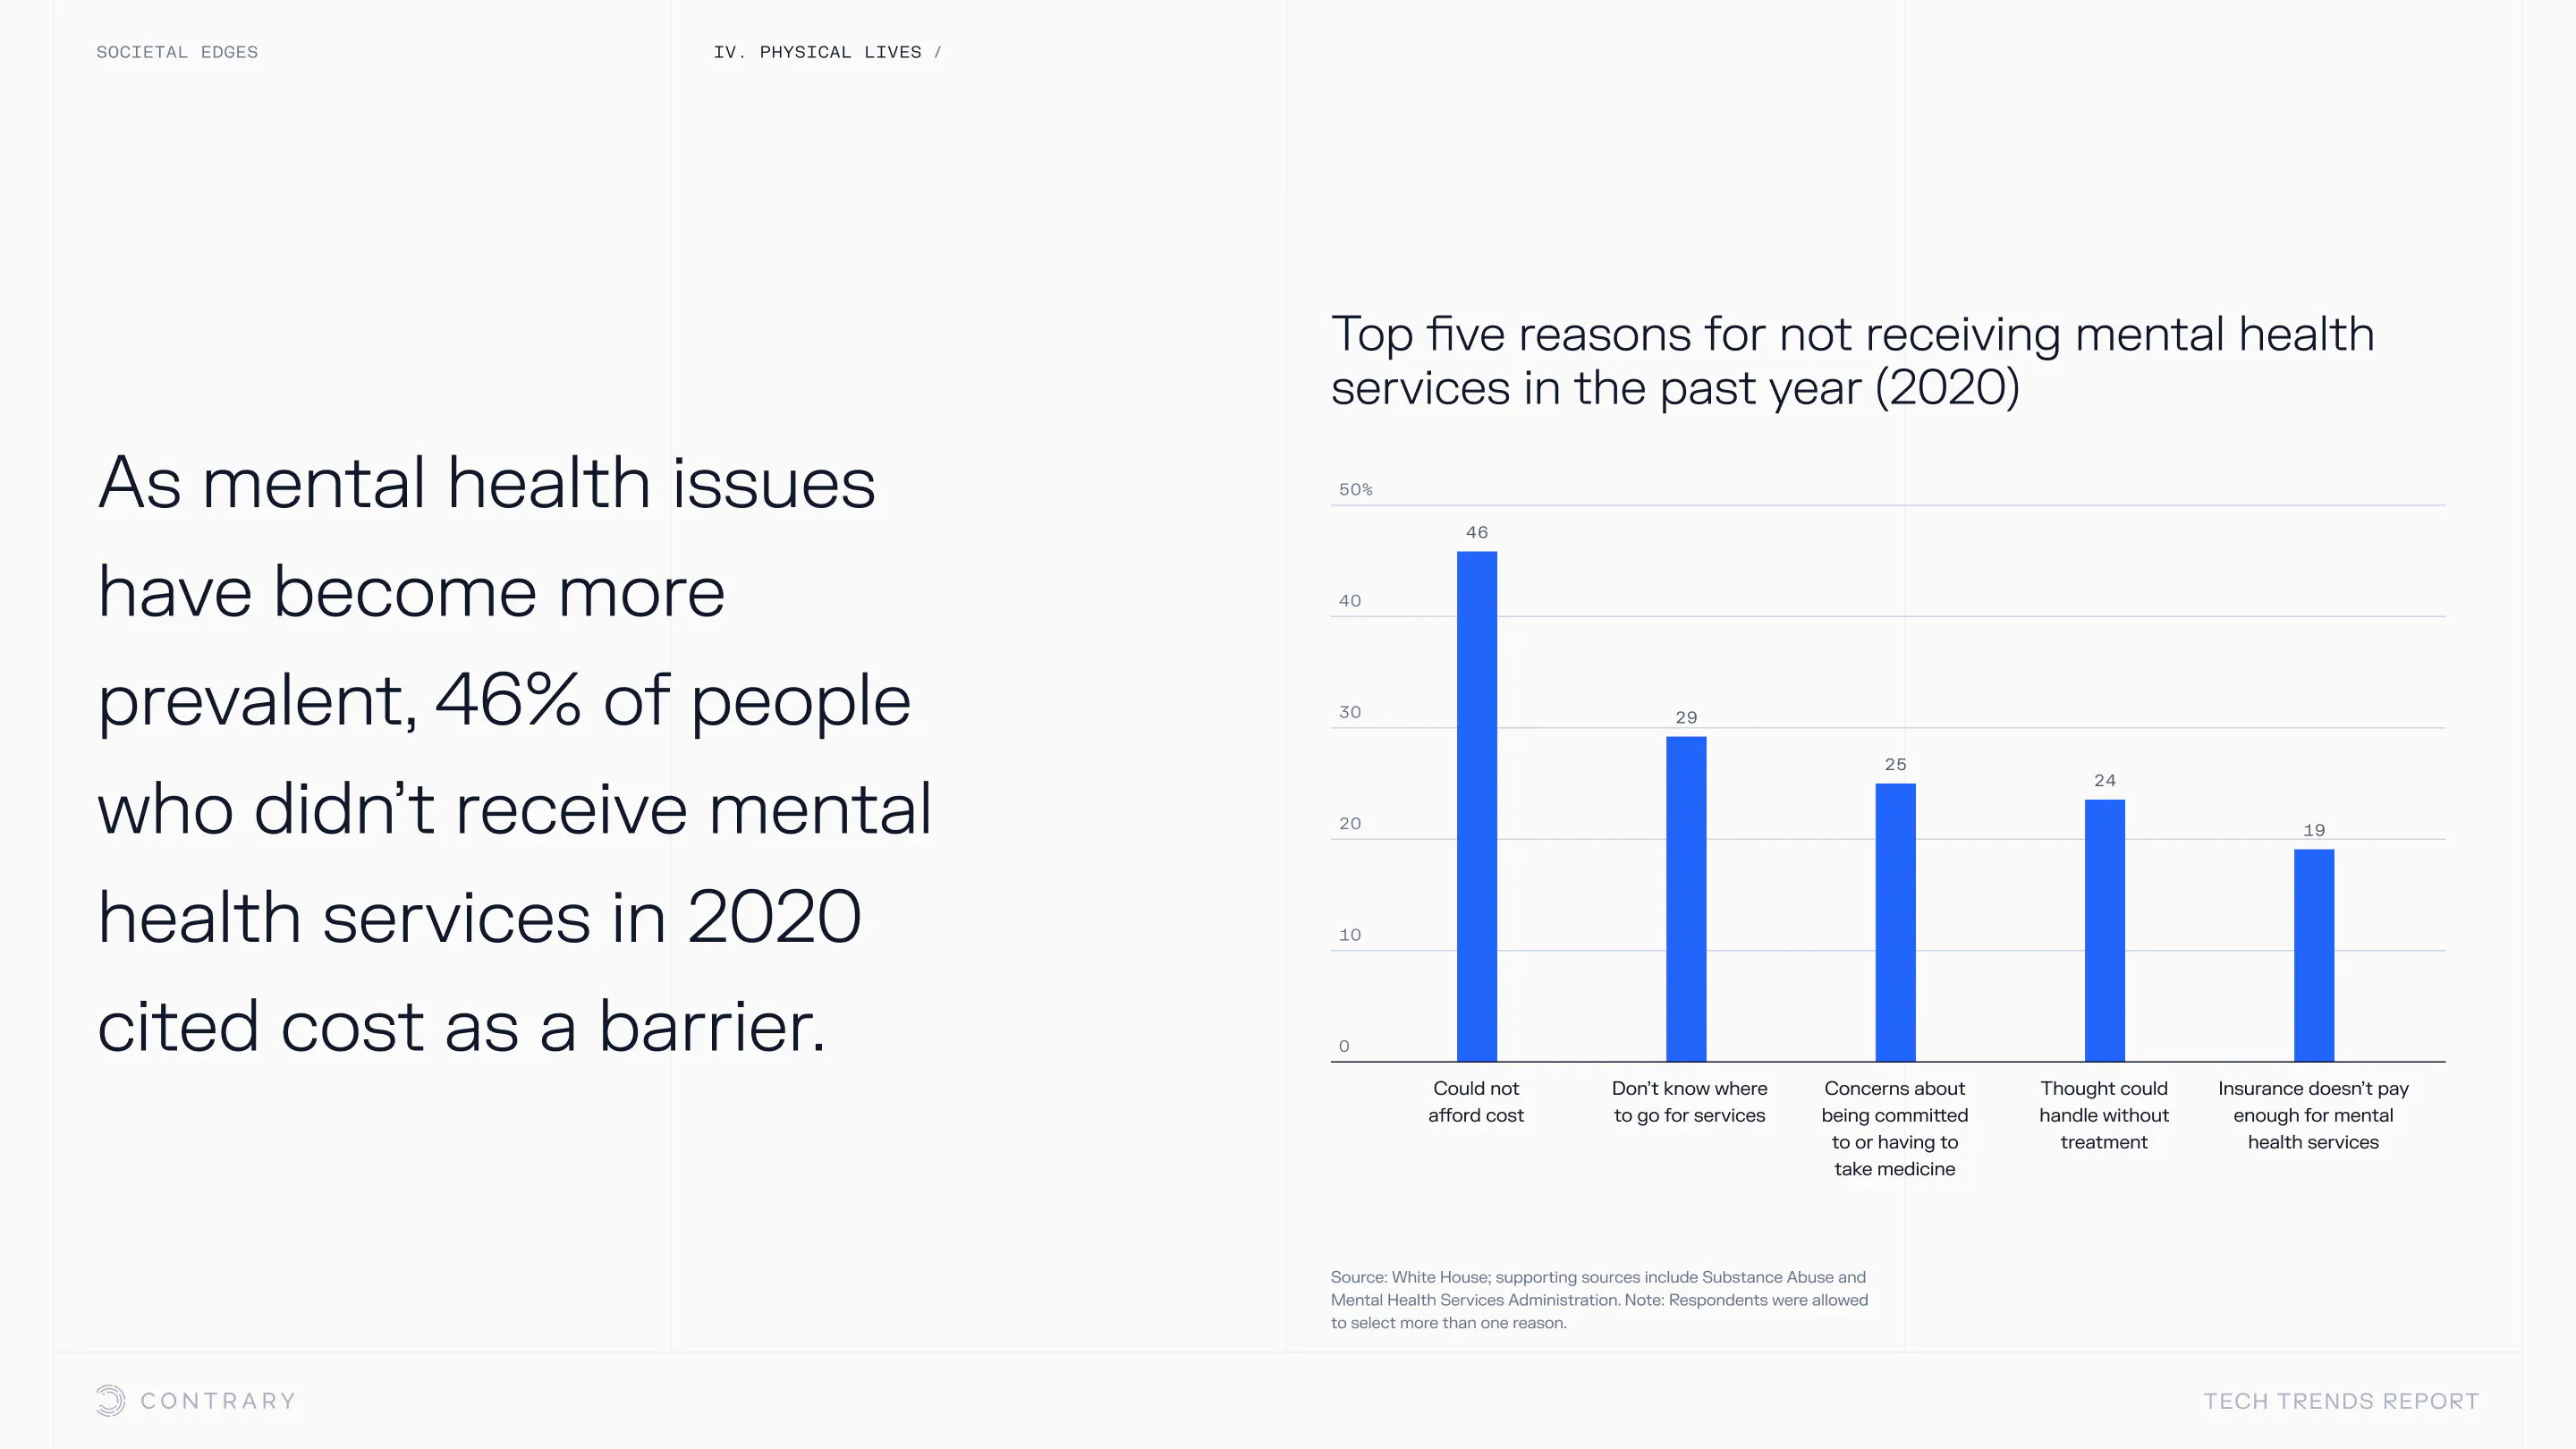

An aging population is bringing up a range of increased concerns, from mental health to disease control. Obesity and gastrointestinal cancers are plaguing younger generations. The cutting edge is tackling a system that has unhealthiness woven into it.